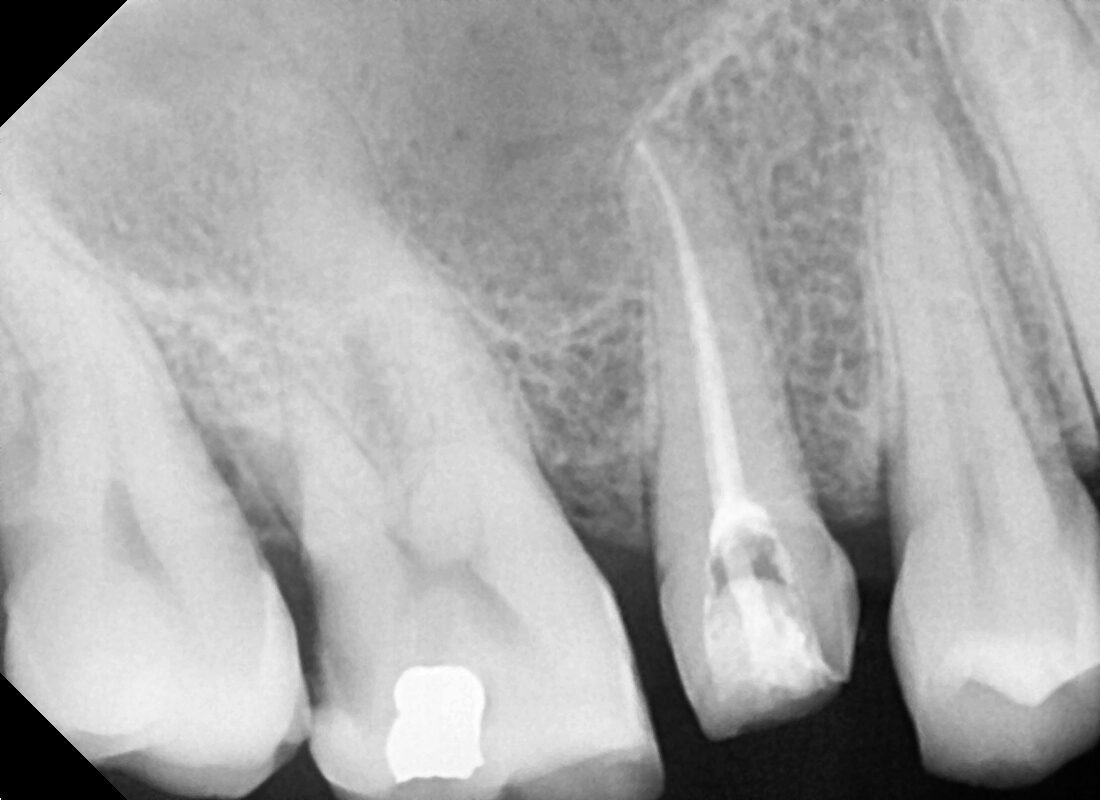

PRE RADIOGRAPH